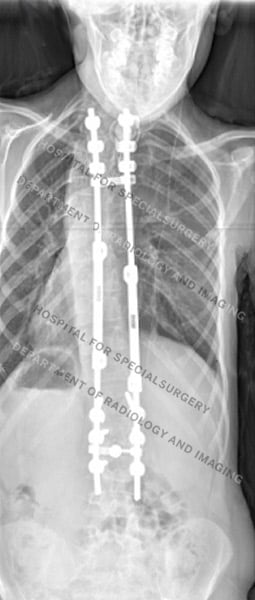

Posteroanterior (back-to-front) X-rays of dystrophic scoliosis (first image) and nondystrophic scoliosis (second image) after surgery

- Spinal fusion for scoliosis and, if present, kyphosis. This surgery involves realigning the spine and using metal rods and screws with bone grafts to achieve fusion.

Surgery to correct a dystrophic scoliosis curve can present special challenges, including the need to correct a kyphotic (rounding of the back) curve at the same time. These surgeries also carry a risk of pseudoarthrosis or non-union. To help minimize this risk, orthopedic surgeons at HSS use autograft from the patient’s iliac crest bone (part of the pelvis) to achieve the fusion, as opposed to the allograft often used in other scoliosis surgeries. These complicating factors often necessitate more than one surgery.